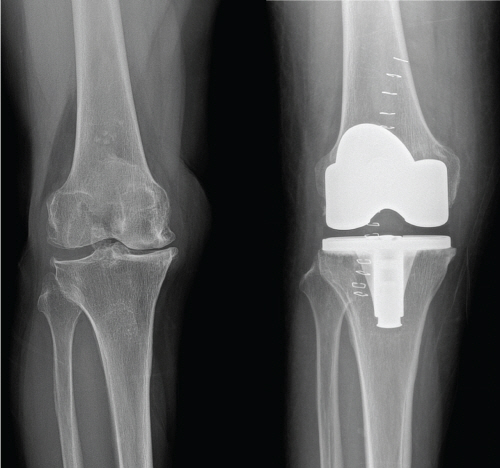

±â»ç ³»¿ë »ðÀÔ À̹ÌÁö

[¿Óóµ¥Àϸ®] ÃÖ±Ù Æò±Õ ¼ö¸í ¿¬ÀåÀ¸·Î ÀÎÇØ ÅðÇ༺°üÀý¿° ȯÀÚµéÀÇ ¼ö°¡ Å©°Ô ´Ã¾î³ª¸é¼­ Àΰø°üÀý ¼ö¼úÀ» ¹Þ´Â »ç¶÷µéÀÇ ¼öµµ ºü¸¥ ¼Óµµ·Î Áõ°¡Çϰí ÀÖ´Ù. ÅðÇ༺ °üÀý¿°ÀÇ Ä¡·á´Â ¿îµ¿, º¸Á¶±â, ¹°¸® Ä¡·á ¹× ¾à¹° Ä¡·áµîÀÌ ÀÖÀ¸¸ç, ÀÌ·± º¸Á¸Àû Ä¡·á¿¡ ¹ÝÀÀÇÏÁö ¾Ê´Â °æ¿ì ¼ö¼úÀû Ä¡·á¸¦ ÇÏ°Ô µÈ´Ù.

½ÉÇÏ°Ô °üÀýÀÌ ¼Õ»óµÇ¾úÀ» °æ¿ì¿¡´Â ¿©·¯ °¡Áö ¼ö¼ú Áß Àΰø°üÀý ¼ö¼úÀ» ±ÇÀ¯ÇÏ°Ô µÇ´Âµ¥ ÅðÇ༺ °üÀý¿° Ä¡·áÀÇ ¸¶Áö¸· ¹æ¹ýÀ̱⠶§¹®¿¡ Á¤È®ÇÑ Áø´Ü°ú ¼ö¼ú °áÁ¤ÀÌ ÇÊ¿äÇÏ´Ù. °Ç°­º¸Çè½É»çÆò°¡¿øÀÇ ÀÚ·á¿¡ µû¸£¸é Àΰø°üÀý ¼ö¼ú °Ç¼ö´Â 2010³â 75,000¿©¸íÀ¸·Î 10³â°£ 5¹è ÀÌ»ó Áõ°¡ÇßÀ¸¸ç ÀÌ´Â Àα¸ ½Ê¸¸ ¸í´ç 154¸íÀ¸·Î ¼±Áø±¹ ¼öÁØÀÌ µÇ¾ú´Ù. ¼ö¼úÀÇ Áõ°¡·Î ÇÕº´Áõ ¹× ºÎÀÛ¿ë¿¡ ´ëÇÑ ÀνÄÀÌ ºÎ°¢µÇ¾úÀ¸¸ç Á¡Â÷ Àΰø°üÀý Àçġȯ¼úÀÇ ºóµµ ¿ª½Ã Áõ°¡ÇÏ´Â Ãß¼¼ÀÌ´Ù.

°¡Àå ´ëÇ¥ÀûÀÎ ¿ÀÇØ·Î Àΰø°üÀý ¼ö¼ú ÈÄ ¹«¸­ÀÌ ±¸ºÎ·¯ÁöÁö ¾Ê´Â »¸Á¤´Ù¸®°¡ µÈ´Ù´Â °ÍÀÌ´Ù. ÇÏÁö¸¸ ÀÌ´Â »ç½ÇÀÌ ¾Æ´Ï´Ù. ÃÖ±Ù °³¹ßµÈ ÀϺΠÀΰø°üÀý »ðÀÔ¹°Àº ¿ì¸®³ª¶ó »ç¶÷µé°ú °°ÀÌ ÁÂ½Ä »ýȰ±¸Á¶¿¡ ¾Ë¸Â°Ô °³¹ßµÇ¾î ¼ö¼ú ÈÄ ¹«¸­ÀÇ ±ÁÇôÁüÀ» ÃÖ´ëÈ­ ÇÒ ¼ö ÀÖ´Ù.